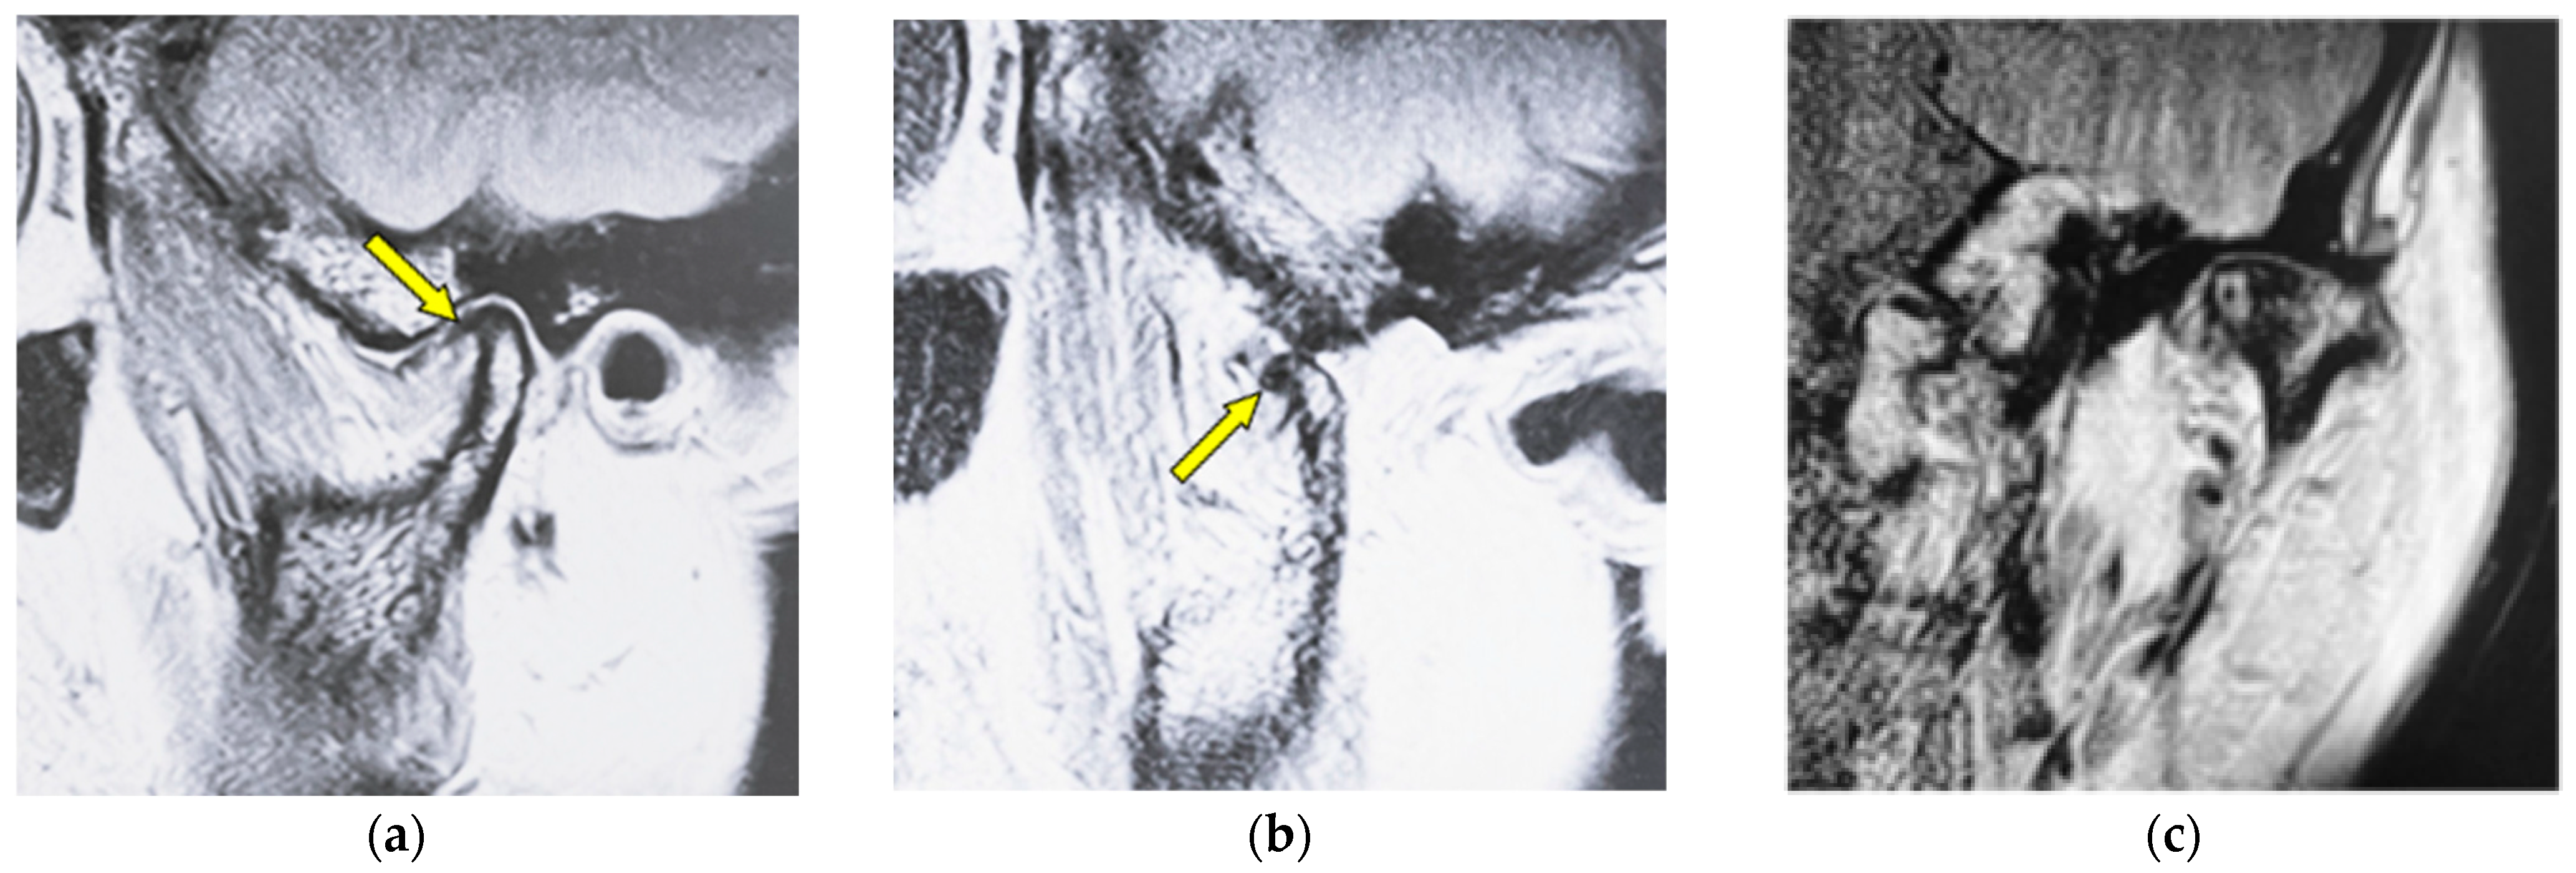

Figure 3 shows MR images of a 53-year-old woman with osteophyte (left TMJ). Sagittal oblique cross-section imaging (proton-density-weighted) shows anterior disc displacement in the mouth-closing position (Figure 3a) and in the mouth-opening position (Figure 3b).

MR image (proton-density-weighted) of a 53-year-old woman (disc displacement without reduction, left disc): (a) sagittal oblique cross-section imaging in the mouth-closing position; (b) sagittal oblique cross-section imaging in the mouth-opening position; (c) coronal oblique cross-section imaging in the mouth-closing position. The arrow shows the part with an osteophyte.